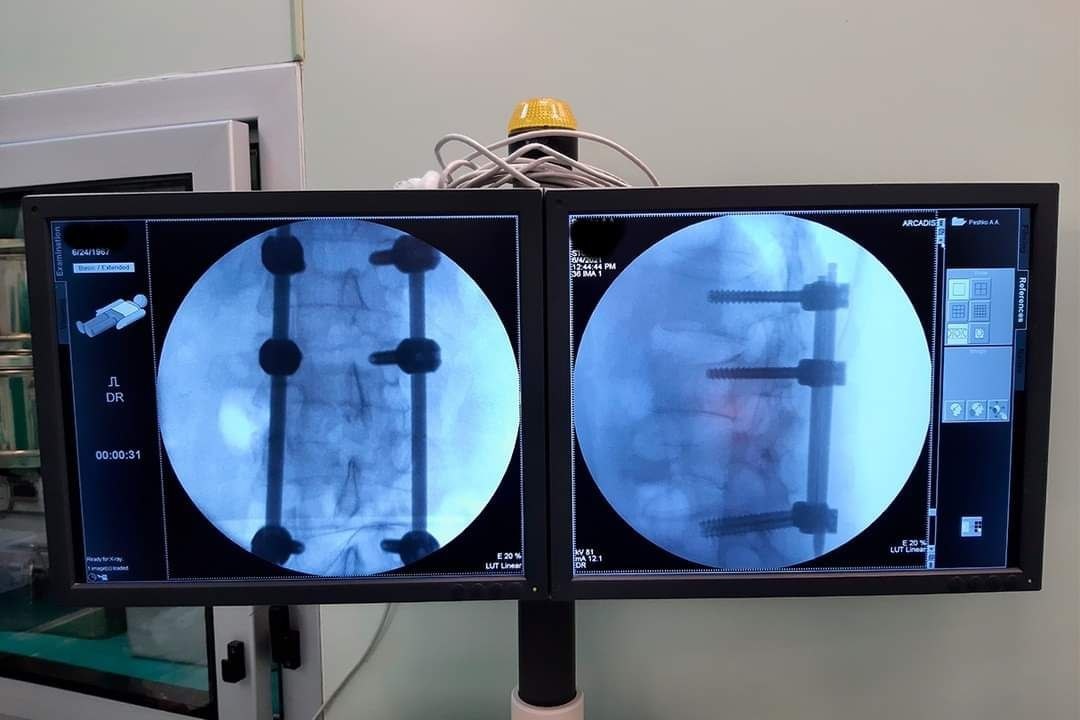

В РНПЦ травматологии и ортопедии разработали новый метод малоинвазивного хирургического лечения, сообщает Минздрав.

Метод подойдет пациентам с повреждениями и заболеваниями грудного и поясничного отделов позвоночника.  Для лечения будут применять чрескожный транспедикулярный фиксатор позвоночника. Конструкцию сделали на основе полиаксиального транспедикулярного винта с двойной фиксацией с необходимым монтажным инструментарием.